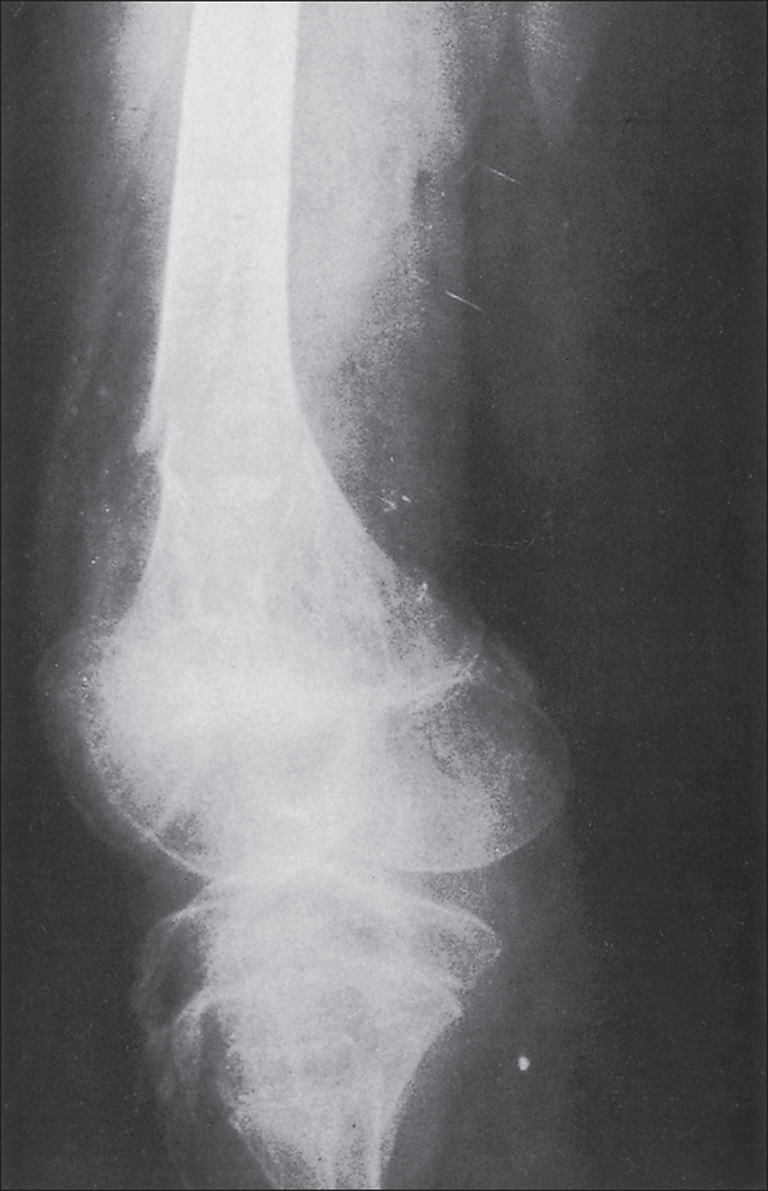

The more extensive the burn and the greater the number of complications, the longer the patient may be confined to bed and relatively immobile. The onset of osteoporosis is accelerated, and its intensity is more marked in the burn illness that features a hypermetabolic state. Klein et al. found that osteoblasts and probably osteocytes underwent apoptosis in response to the glucocorticoid stress hormones. The overall effect of burn is catabolic, and muscle wasting is also noted. If a single extremity of an otherwise normal person is immobilized for a long time because of local trauma, as with a fracture, loss of bone density can be easily seen on plain radiographs. So, with burns isolated to the extremities, the bones of affected extremities become osteoporotic, and in persons with generalized burns, the bones of deeply burned extremities may show more profound mineral loss than is observed in nonburned extremities or in the axial skeleton ( Fig. 41.1 ). This tendency for more osteoporosis in severe burns was also noted by Pandit et al., who found that 56% of postburn patients had radiographic evidence of osteopenia. Van der Wiel et al. found in an x-ray absorptiometry study of 16 adults with fractures of one tibia that there was eventual loss of bone mineral density in the contralateral femur and in the lumbar spine but to a lesser degree than in the ipsilateral femur. These findings, although not strictly analogous to those observed in burns, nevertheless point to the occurrence of generalized osteoporosis in other trauma states and the difference in loss of bone density relative to local factors. In fractures or in burns, impaired mobility and local hyperemia could account for this difference.

(A) Advanced osteoporosis in the hands of a 14-year-old boy 9 months after a 100% total body surface area burn. All growth plates are open. (B) At 24 months after injury, osteoporosis persists, and there is irregular closure of the metacarpal and phalangeal growth plates. (C) At 8 months after injury, the growth plates of the distal tibiae and fibulae remain open. (D) At 24 months after injury, the distal growth plates of the tibiae and fibulae are closed. Other major growth plates remain open. Osteoporosis is unchanged.